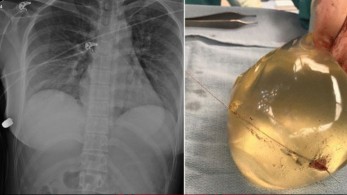

Καναδάς: Εμφύτευμα σιλικόνης “απέκρουσε” σφαίρα!

22.4.2020

• #ΚΑΝΑΔΑΣ

• #ΥΓΕΙΑ